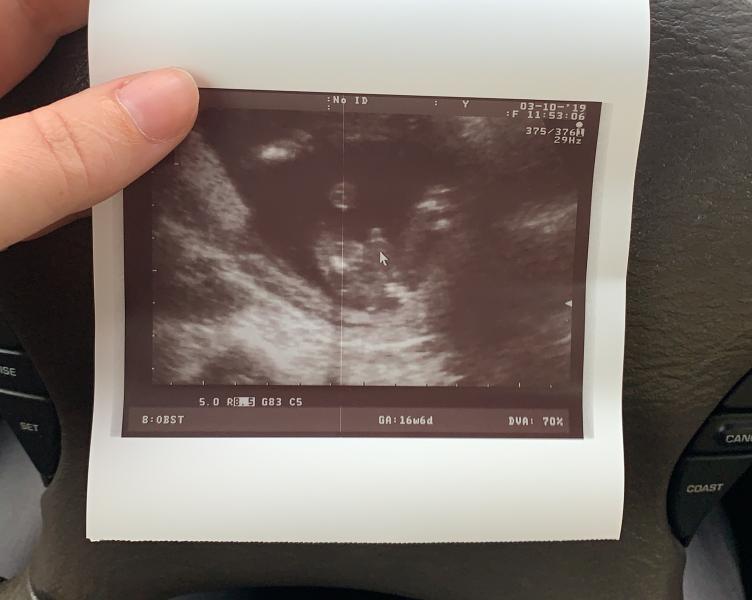

МАЛЬЧИК!!!! МАЛЬЧИК!!! У нас МАЛЬЧИК!!!! 😁😊🤗🥳🥳🥳 Думала расстроюсь (ведь так хотели девочку), но я ТАК ДЕВОЧКИ РАДА!!! Два сына, два крыла! ❤️🥰

У меня срок 19 недель и 6 дней, вес малыша должен быть до 240 г, а мой весит 305 г.